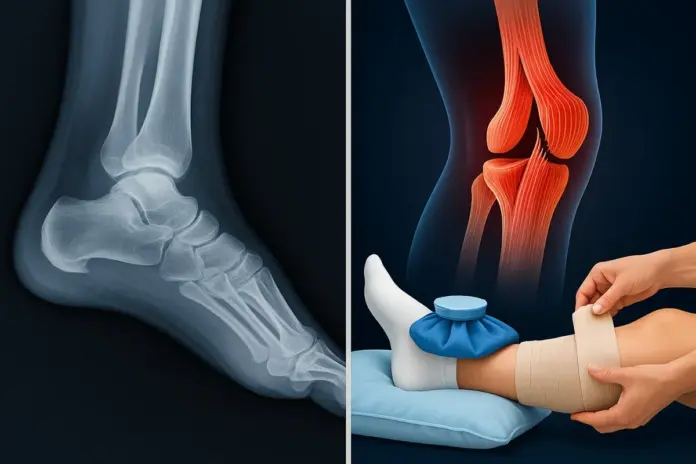

RICE stands for rest, ice, compression, and elevation, the first defense against pain and swelling. Stopping activity gives bones and ligaments time to begin repair naturally. Ice applied for 15–20 minutes every hour soothes inflammation and numbs soreness. Compression using elastic bandages controls swelling but must not stop circulation.

Elevating the affected limb above heart level helps fluid drain away, easing pressure. Following RICE properly supports both fracture diagnosis and treatment phases and early ligament rupture recovery. When used early, it prevents stiffness and limits further tissue injury. Still, not every pain stops with RICE alone; some need deeper care.